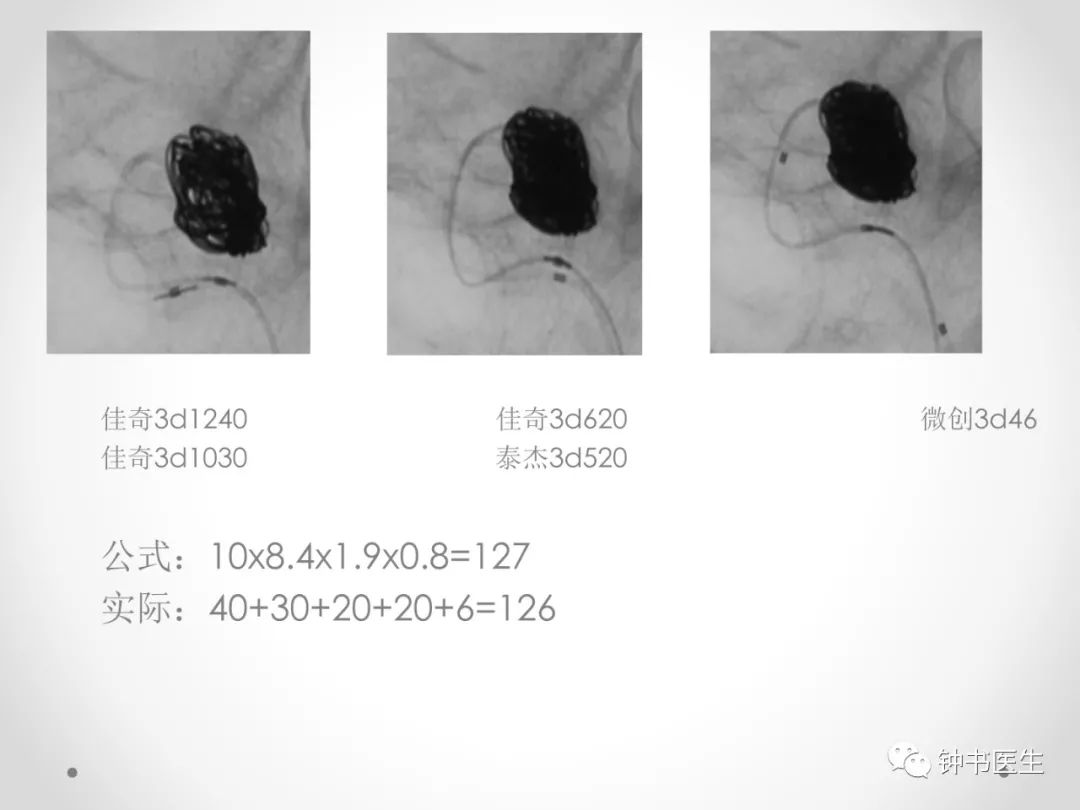

长x宽x1.X=弹簧圈总长度

1.X:X为动脉瘤平均直径

公式合理性:栓塞致密性(33%)即4/3πR3/3

4mm直径动脉瘤:

4/3πR3/3=4x3.14x8/9=21 4x4x1.4=22 偏大4%

10mm直径动脉瘤:

4x3.14x125/9=174 10x10x2=200 偏小15%

20mm直径动脉瘤:

4x3.14x1000/9=1395 20x20x3=1200 偏小14%

动脉瘤越小栓塞越致密,越大越难以致密,符合临床操作实际和远期随访结果。